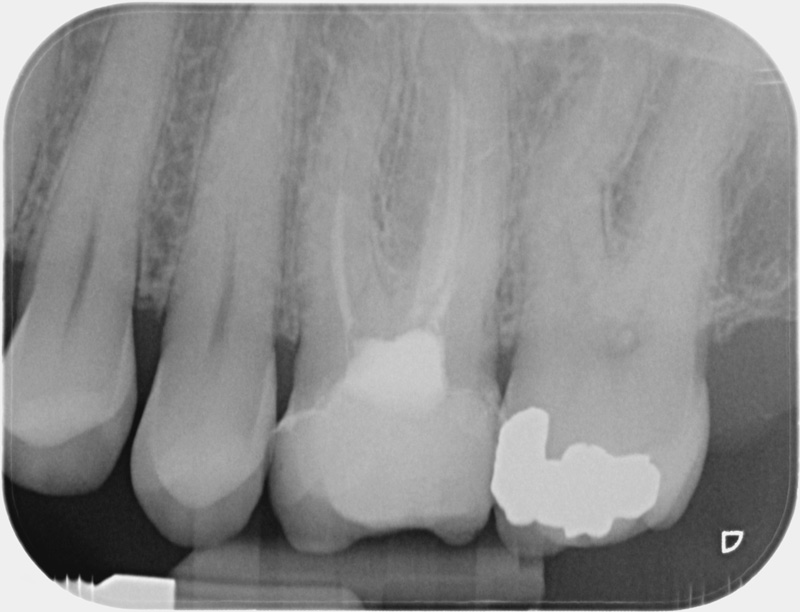

Après

• Apexification : Chez le jeune enfant, une dent immature victime d’un traumatisme ou d’une carie volumineuse peut poser problème. Si la pulpe agressée se nécrose, alors la racine ne s’édifie plus et une lésion inflammatoire se développe au niveau osseux. L’apexification, par apposition d’un matériau biocompatible dans la racine, cherche à induire la formation d’une barrière artificielle à l’extrémité de celle-ci, et permettre la cicatrisation de la lésion dans le but de maintenir la dent en bouche à long terme.

Avant